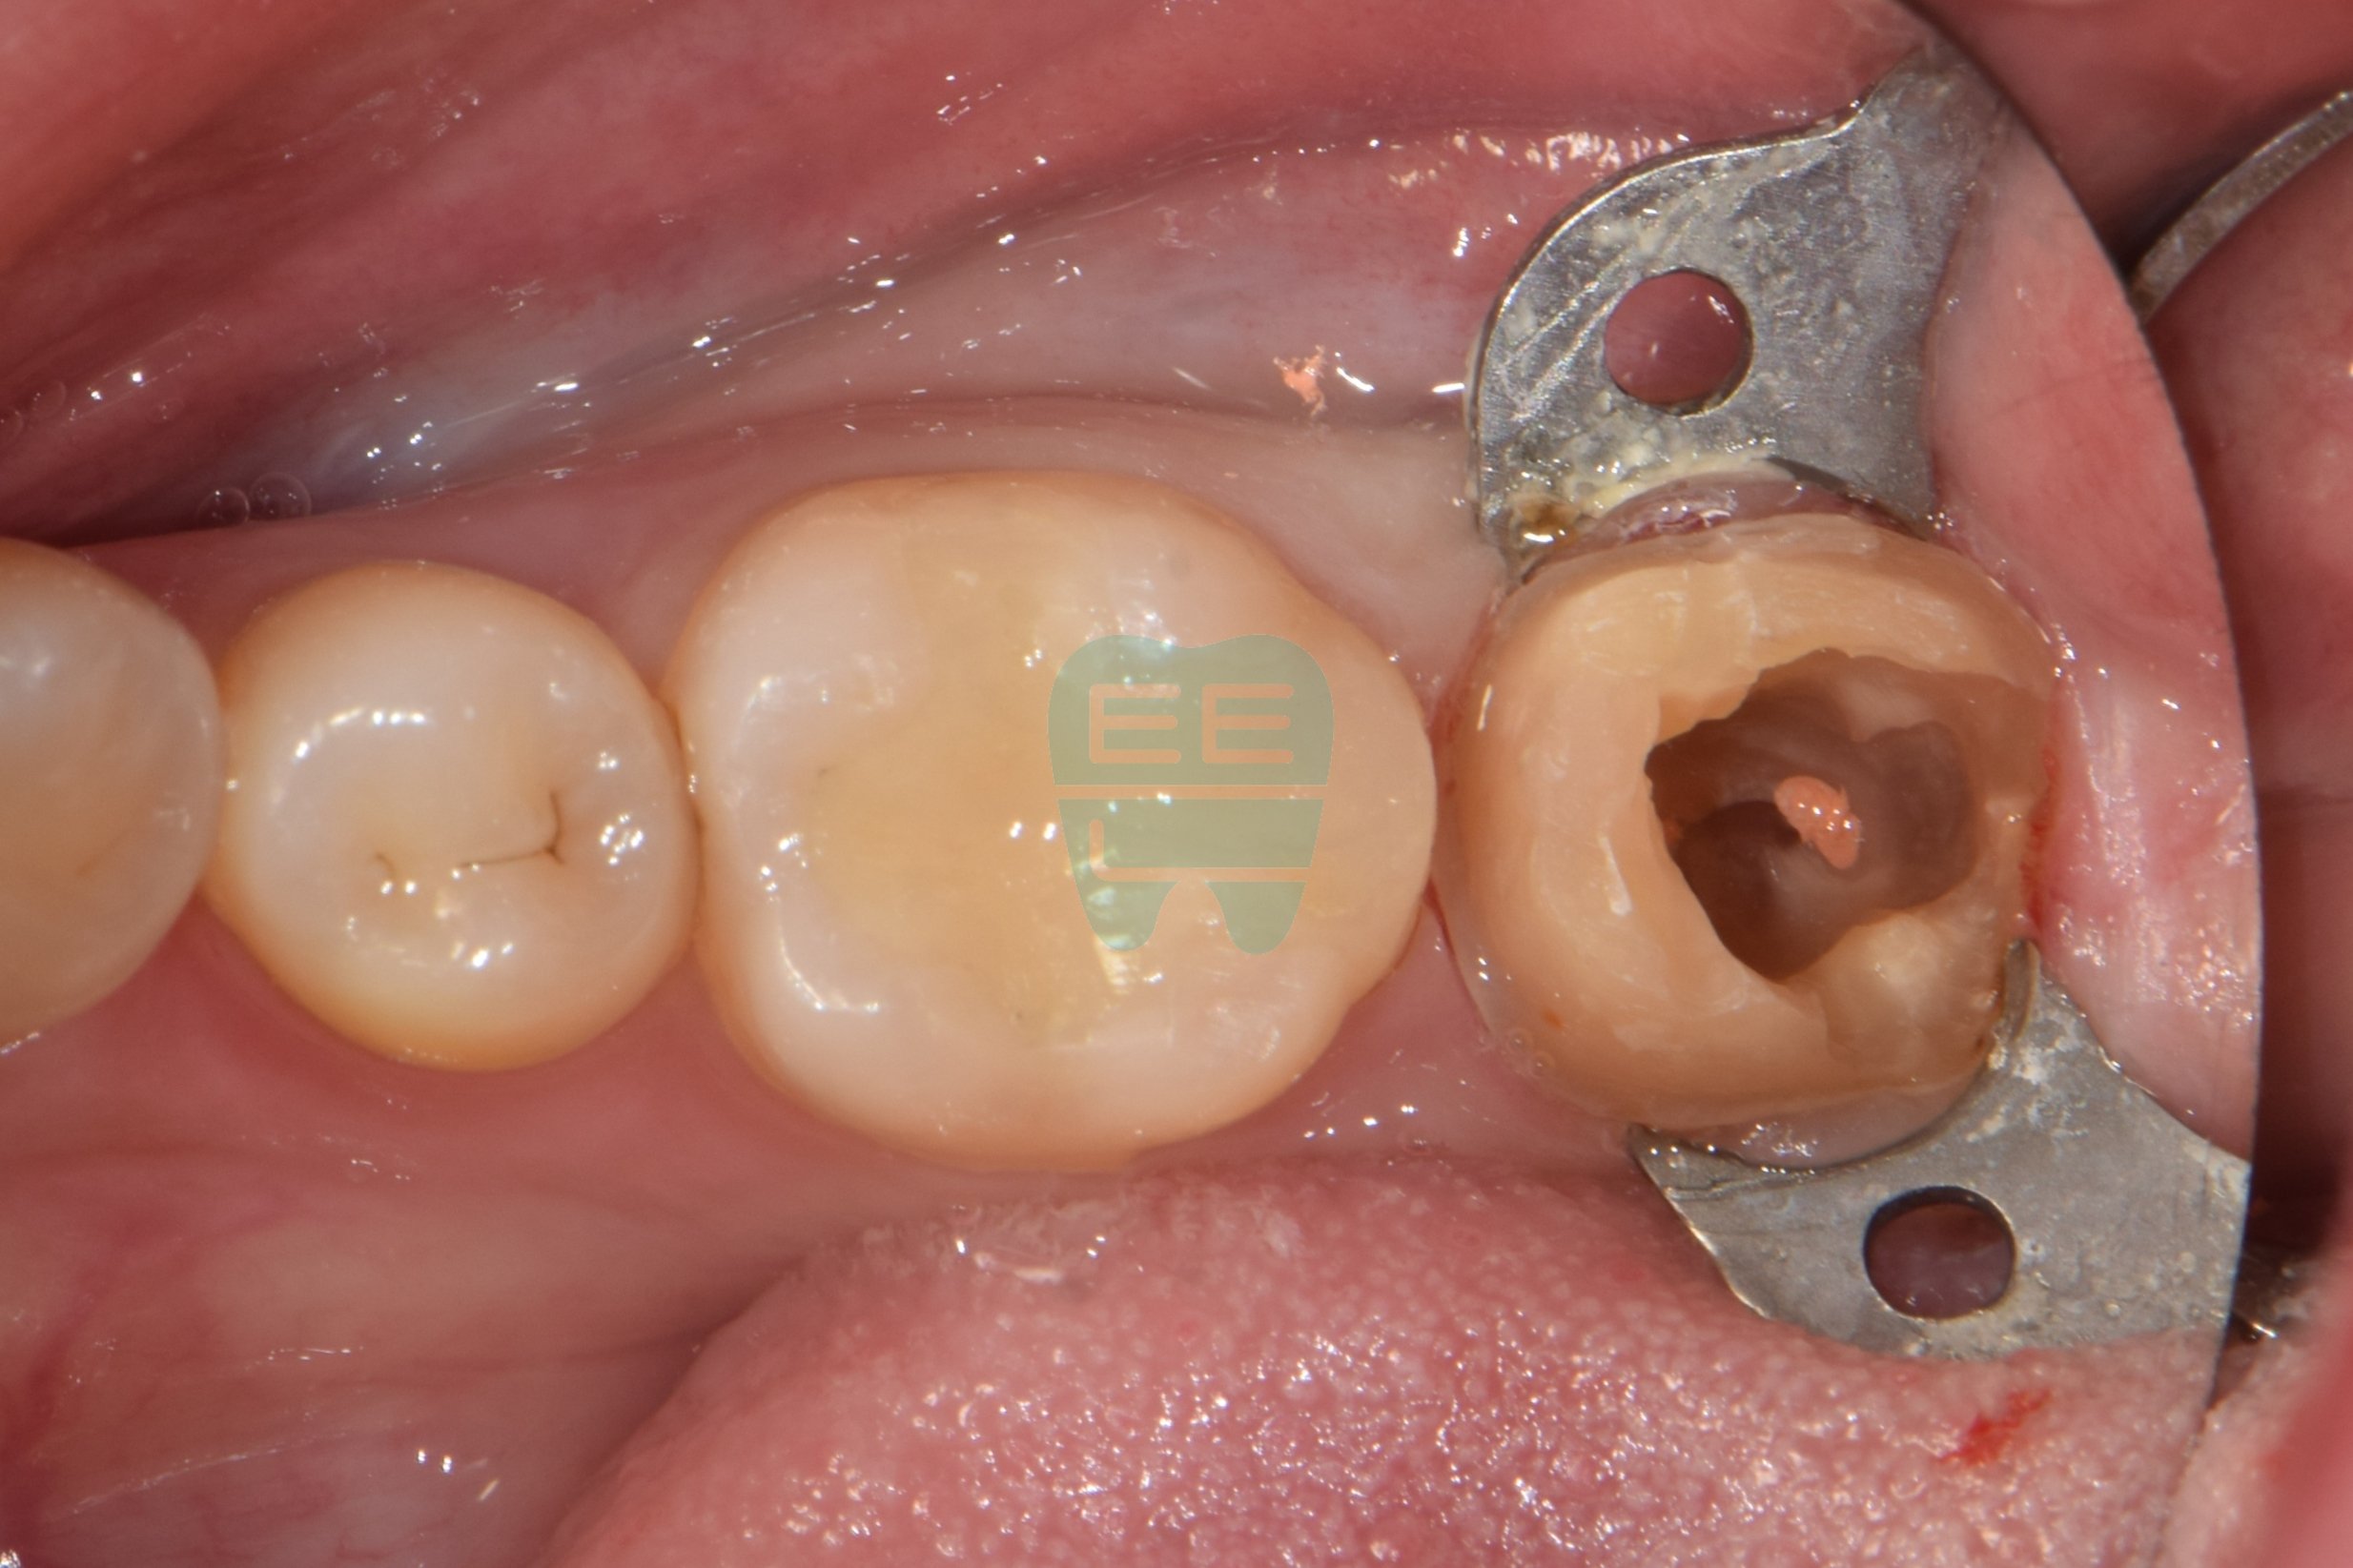

크라운 하방 2차우식 치료를 위한 레진코어 빌드업 방법

초진상태로 찝찝한 냄새가 나신다 하심크라운 제거후 상태로 파란색 코어가 관찰됨코어 제거후 상태로 원심 2차우식으로인한 leakage로인한 악취로 진단함충치와 레진코어를 모두 제거한 상태러버댐과 원심 격리를 위한 매트릭스 밴드를 장착중인 모습러버댐 하에 원심 레진wall을 형성한 모습

사진 4